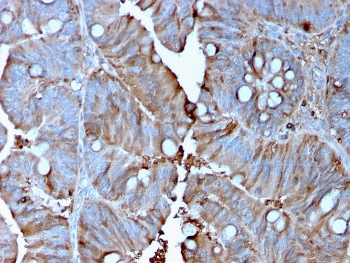

IHC staining of FFPE human colon carcinoma with MerTK antibody (clone TPKR-1). HIER: boil tissue sections in pH9 10mM Tris with 1mM EDTA for 10-20 min and allow to cool before testing.